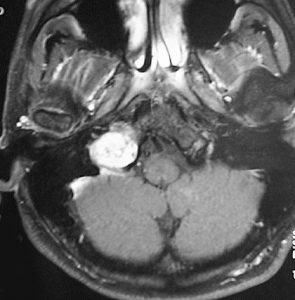

症例:頸静脈孔から頭蓋内へのもの

頸静脈孔を中心に頭蓋底骨の破壊 erosionがみられます。小脳延髄角部に進展して延髄を圧迫しています。聴神経を圧迫して聴力低下で発見された,迷走神経鞘腫です。頸静脈孔内発生のものは脳槽内の迷走神経根から腫瘍を剥離することができます。

手術直後のMRIです。頸静脈孔より深い位置にある腫瘍まで摘出しようとすると,舌咽,迷走,副神経を損傷しますから,最深部の部分だけ残して摘出しました。

手術後14年が経過しますが,無治療で残存腫瘍は縮小しました。術後神経鞘腫の自然経過ではよく観られることです。

ですから,無理して全摘出しない。